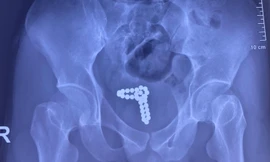

TPO - Đang thử 'cảm giác lạ' thì chuỗi bi kim loại tuột vào niệu đạo khiến nam thanh niên phải nhập viện cấp cứu trong tình trạng tiểu xuất huyết. Các bác sĩ đã phải mổ bàng quang, lấy dị vật ra ngoài.